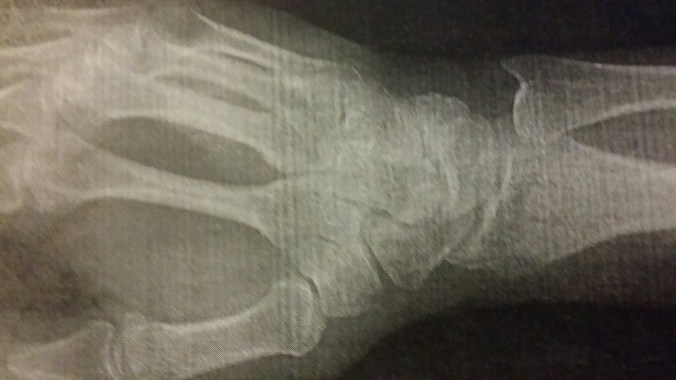

Jake thought these x-rays of my wrist and hand were awesome. He got to stand in the little radiology room and watch the tech take them. Neither of us were as impressed by the sound my apparently in stable bones made (think “click, click, CLICK!”) when the doctor was rotating my hand and wrist in various directions! It was really pretty freaky sounding!!!